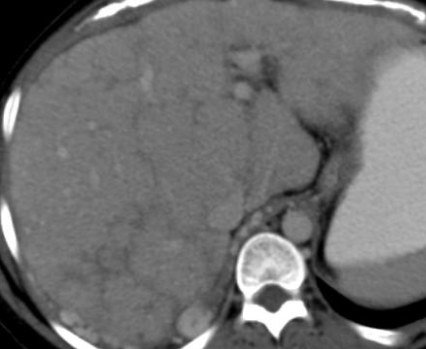

CT

- Foie hétérogène, troubles de perfusions

- Thrombose de sus-hépatiques

- Hypertrophie du caudé (drainage propre)